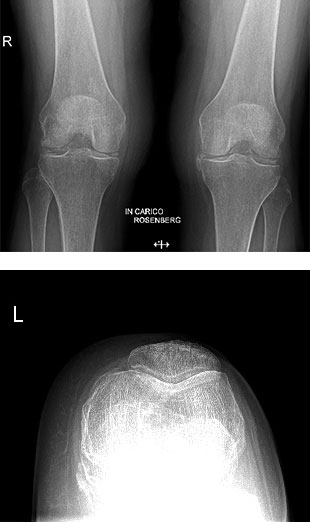

Paziente donna di 67 anni, affetta da gonartrosi tricompartimentale sinistra aggravata da calcificazione dei menischi, trattata con protesi totale mini invasiva del ginocchio a conservazione del legamento crociato posteriore.